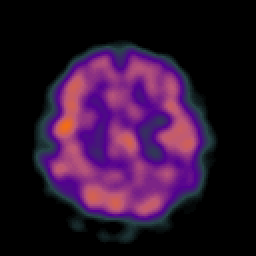

Alzheimer's Disease: SPECT/fMRI overlay -- Slice #8

Keith A. Johnson (keith@bwh.harvard.edu), J. Alex Becker (jabecker@mit.edu)